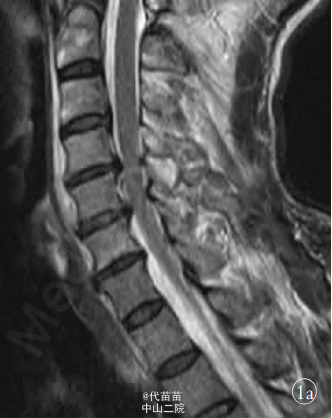

患者,男,61岁。 因高处坠落致颈部疼痛 2h余入院。 查体:C4-C6棘突压痛明显,活动受限,稍有肿胀,双上肢感觉麻木伴有痛觉过敏,双侧肱二头肌肌力Ⅳ级,双手握力下降,双下肢感觉活动可,肢端感觉血供可。入院时实验室检查均未见明显异常。 MRI 检查显示 C3-C7 椎间盘后突伴 C4-C6 平面椎管狭窄,颈髓受压,髓内见小片高信号影,颈椎退行性改变(图1a)。 诊断:①颈椎病;②颈髓损伤。 手术:采用全身麻醉,取颈部右侧斜行切口,长约 6 cm,逐层切开皮肤、颈阔肌,沿气管食管与胸锁乳突肌、颈动静脉鞘间隙分离暴露椎前筋膜,分离椎体前筋膜,摄定位X线片,将前纵韧带切开,显露病变椎体及椎间盘, 先用角度刮匙和髓核钳切除病变段椎间盘及上下 终板,用高速磨钻行病变椎体大部分切除,显露硬脊膜和致压物。 小心分离致压物,彻底解除脊髓压迫。 植入大小适中填满松质骨的钛网, 再将长短合适的颈前路钢板系统通过螺丝钉固定于开槽减压区上下方椎体上。 C 形臂 X 线机透视证实钢板系统位置正确后,切口内置负压引流管,逐层缝合切口。 手术顺利,出血约 200 ml。 术后 48 h 切口引流量约 50 ml,拔除引流管。术后复查 X 线片示内固定位置可(图 1b,1c)。术后查体:双上肢感觉无麻木,双侧肱二头肌肌力Ⅳ级强,双手握力Ⅳ级,双下肢各肌群肌力Ⅴ级,感觉活动可。 术后第 5 天突发神志不清 ,躁动不安 ,查体 :双上肢肌 力Ⅲ级 ,双 下 肢 肌 力0 级,病理反射未引出。 急查头颅 CT、血电解质、血气分析等 均未发现明显异常, 胸部 CT 示双肺下叶炎症伴两侧胸膜反应。 经相关临床科室会诊后转入 ICU 监护,予抗感染,加强龙冲击等对症支持治疗。复查头颅 MRI、DWI、MRA,胸腰椎 MRI均未见明显异常, 颈椎 MRI 示:C4-C6 椎体内固定术后改变,颈髓受压,髓内见小片高信号影(图 1d)。 经外院脊柱外科专家会诊: 颈髓受压影像考虑为内固定产生伪影所致。 术后第10 天,患者情况较前明显好转,转入我科继续抗感染、营养神经、针灸等对症治疗。 查体:神志清,切口愈合良好,平乳头平面以下感觉麻木,双侧肱二头肌肌力Ⅲ级,双下肢股四头肌肌力Ⅰ级,双侧胫前肌、拇长伸肌肌力 0 级,巴彬斯基征阳性,奥本汉姆征阳性。 术后 15 d 双下肢股四头肌、胫前肌肌力较前出现好转。 术后 20 d 双下肢肌群肌力恢复至Ⅲ级水平。 术后45d双上肢肌群肌力Ⅴ级,双下肢肌群肌力Ⅵ级强,已下地步行训练。 近年来, 颈椎前路减压植骨钢板螺钉内固定术已普遍运用于颈椎疾病的治疗中,然而手术后并发症也时有发生。本例患者术后近 1 周突发下肢截瘫,1 个月后又基本恢复,实属罕见。 分析原因:①考虑术后血肿形成,压迫脊髓造成相应症状出现。②考虑内植物松动移位。 ③可能与术后感染,脓肿压迫神经组织有关。 然而标准的颈前路手术有 1%~3% 的创口感染率。本例患者术后切口愈合良好,无红肿及液性渗出,颈椎 MRI 检查未见明显脓肿形成。 虽有肺部感染情况发生,但不足以构成对神经系统的损伤,导致截瘫的发生。 仔细回顾病史,患者曾有长年酗酒史,术后出现过意识 模糊,并伴有全身抽搐现象,复查电解质示血钙、血钠有异常,这与截瘫的发生不无关系。 有研究表明,对于长期酗酒患者,酒精戒断容易出现神经及精神方面症状。 而戒断性癫痫发作好发于长期饮酒后造成慢性酒精中毒的男性, 包括老年人在内的各年龄段都有可能发生,可无潜在的异常放电病灶,即头颅 MRI 或 CT检查未见明显异常。本例患者头颅相关检查并无异常,但电解质出现紊乱,且伴有高热、肺炎症状,加之以往有酗酒史,戒断综合征是不得不考虑的原因之一。 患者尽管已行前路钢板内固定,但颈椎的承受力远远未达到生理功能的要求,强烈的全身抽搐极有可能造成对颈髓的损伤,造成难以预计的后果。但神奇的是在截瘫后 1 月余,患者又逐渐恢复正常。查阅相关文献,尚未见有相关类似的报道。 对于此类患者,术前需仔细询问既往史,特别是酗酒史,防止戒断综合征的产生,术后加强监护,加强营养神经等对症支持治疗。